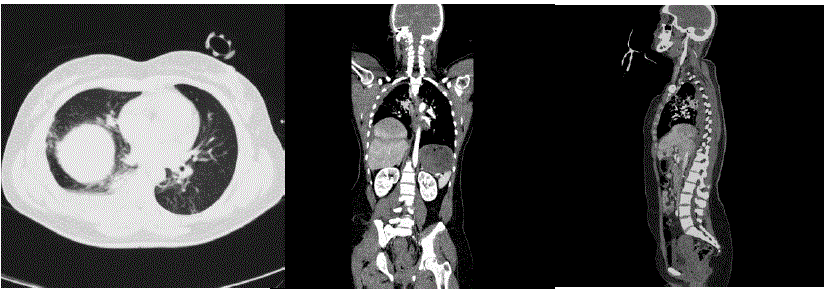

Homem, 27 anos de idade, foi admitido no Serviço de Emergência após colisão de automóvel contra anteparo fixo.

A: via aérea pérvia. Saturação de oxigênio de 92% em ar ambiente

B: dor à palpação do tórax à direita na região inferior e linha axilar média. Hematoma e crepitação no local da dor

C: FC:90bpm e PA: 130x70mmHg.

D: Glasgow de 15. Pupilas sem alterações

E: Diurese clara. Dorso sem alterações. Abdome indolor a palpação.

Realizada tomografia de abdome demonstrada a seguir:

Qual é a melhor conduta?